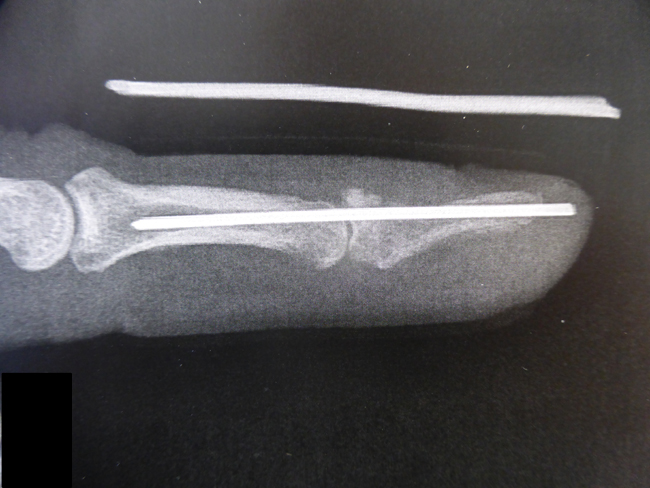

La continuité de l’appareil extenseur et la luxation de la dernière phalange ont été rétablies par une vis

Dans ce cas, la fracture datait de plusieurs jours et il a fallu mettre une broche maintenant à la fois le fragment et l’articulation pour empêcher que le déplacement se reproduise.

- Mallet finger avec fracture et subluxation articulaire

- L’intervention chirurgicale a permis l’immobilisation en bonne position de la fracture et de l’articulation

- La fracture a consolidé et la broche a été enlevée 6 semaines plus tard.